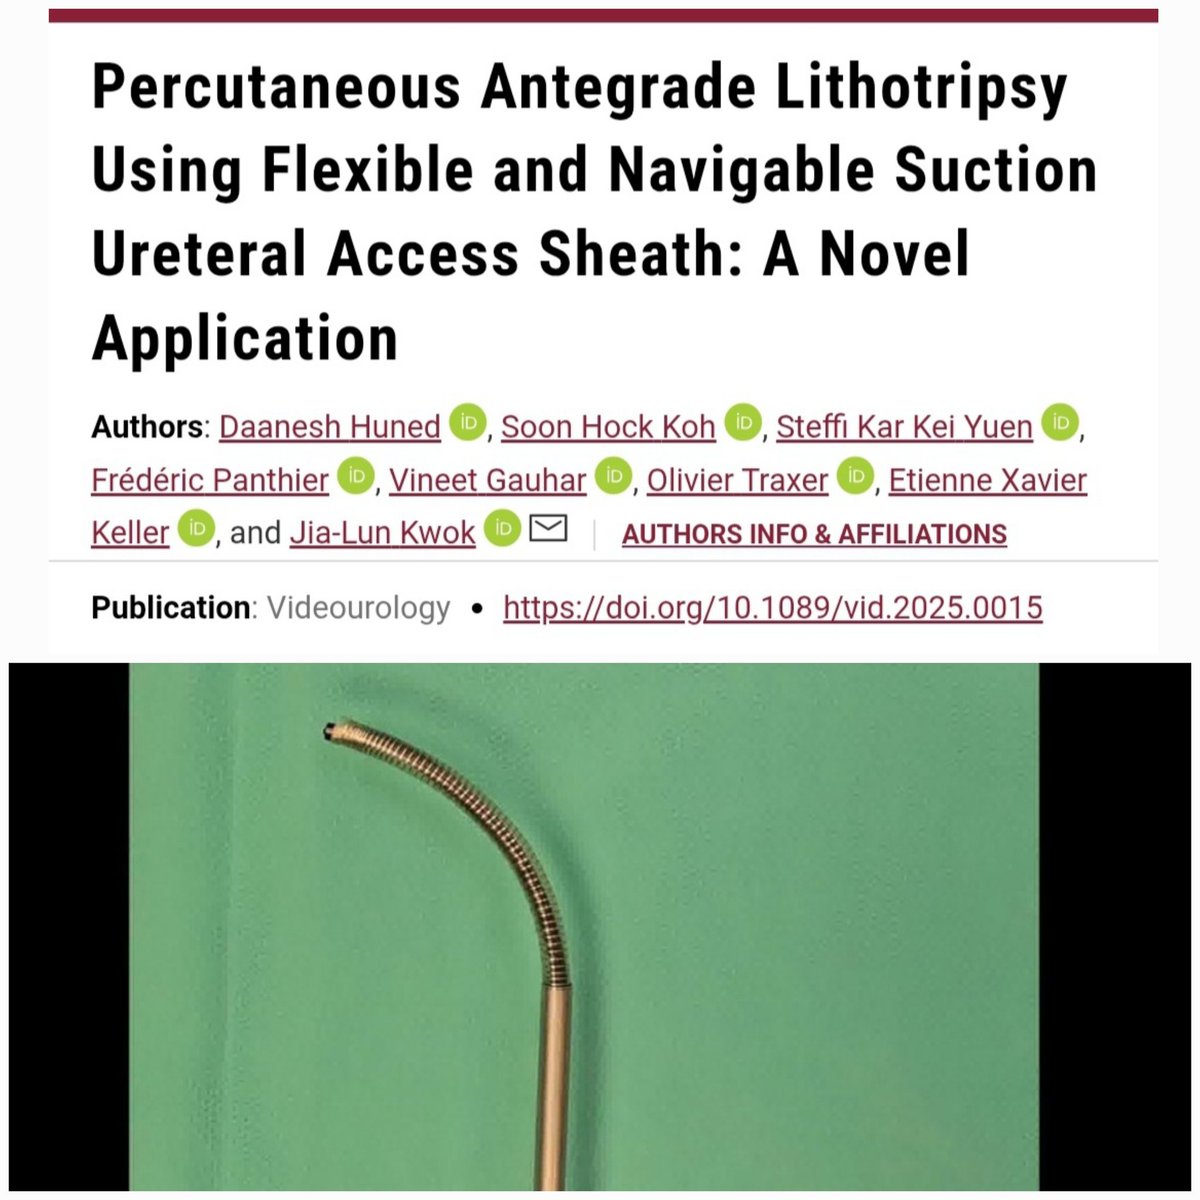

#suction #FANS Percutaneous antegrade approach for large, impacted, upper ureteral stone 🔗liebertpub.com/doi/10.1089/vi… + #FANS & p-Tm:YAG #thulio Steffi Yuen DrG Etienne Xavier Keller Olivier Traxer PEARLS Soon Hock Koh #fpanthier #EAUendourology AUSET YAU ENDOUROLOGY PETRA